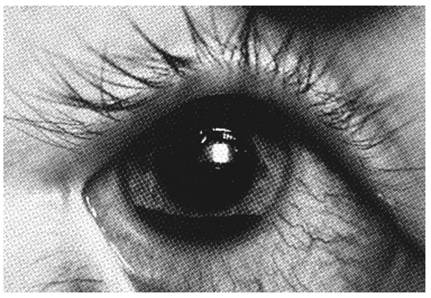

Contuzie oculara cu hipema

PLANSA VI - TRAUMATISME OCULARE

Sunt dominate de prezenta hipemei (sange in camera anterioara-vezi plansa), care se depune decliv, de obicei in unghiul camerular inferior, in functie de pozitia pacientului. Umorul apos are tenta hematica. Hipema se asociaza de regula de cresterea tensiunii intraoculare, datorita blocarii emonctoriilor oculare cu celule hematice. Complicatia cea mai grava, ramane insa impregnatia hematica a corneei, cu pierderea ireversibila a transparentei corneene.